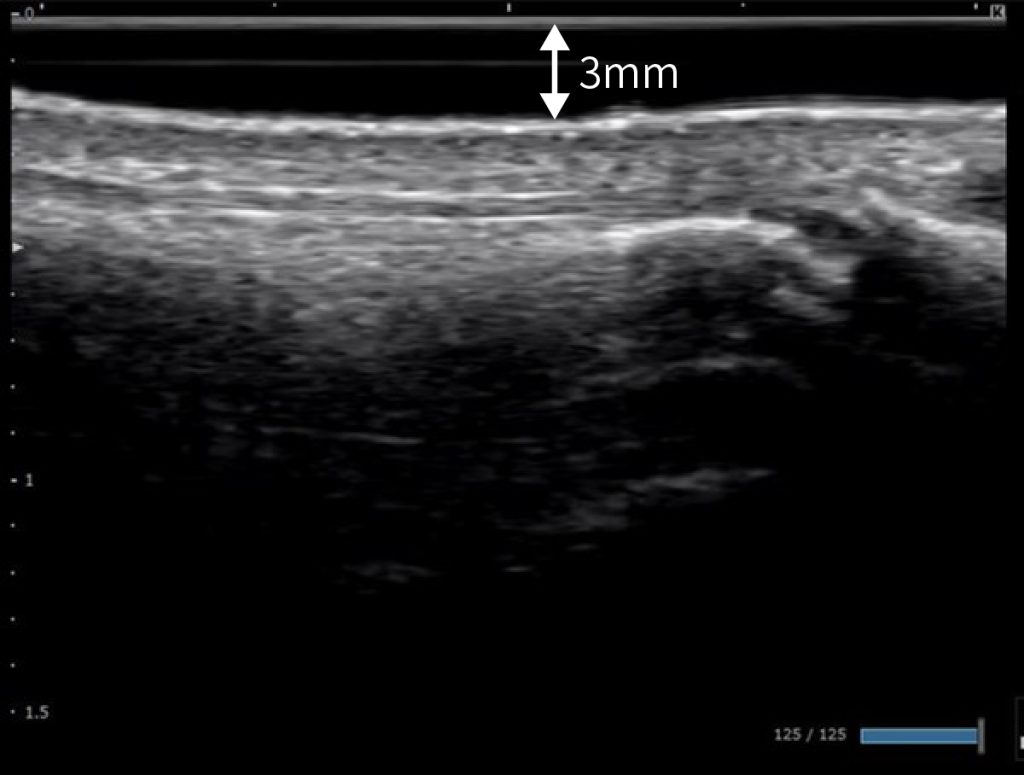

エコーゲルパッドの厚みによる浅層focusの最適化

| エコーゲルパッド | EP-S-03(3mm) EP-S-05(5mm) |

| 診断装置 | コニカミノルタ社製 SONIMAGE HS2 |

| プローブ | L18-4 |

監修 わだ整形外科クリニック 和田誠先生